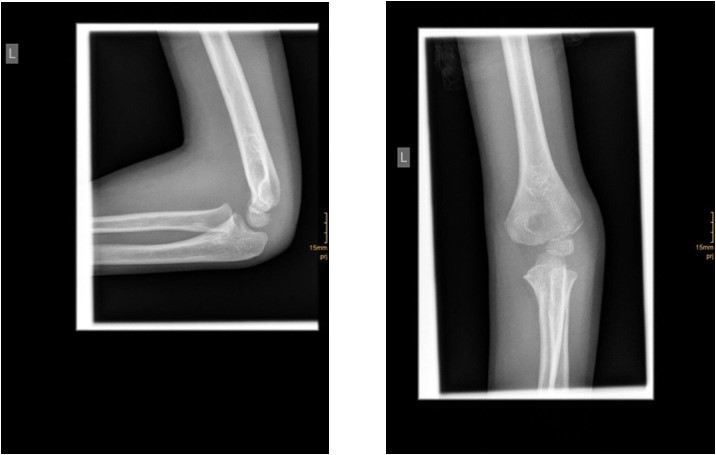

The fracture fragment can be approached by a posteromedial incision that allows good exposure of both the fracture site and the ulnar nerve. Fixation is easily achieved with smooth K-wires or with screws in older adolescents. Two wires are necessary because of the sagittal rotation forces exerted on the fracture fragment by the common flexor muscles. Figure 4 and Figure 5.

Figure 4.14 year old female patient with a elbow dislocation and a dislocated left epicondyle fracture which was treated by open reduction and osteosynthesis with two divergent Kirschner wires (personal collection)

14 year old female patient with a elbow dislocation and a dislocated left epicondyle                 fracture which was treated by open reduction and osteosynthesis with two divergent Kirschner wires (personal collection)